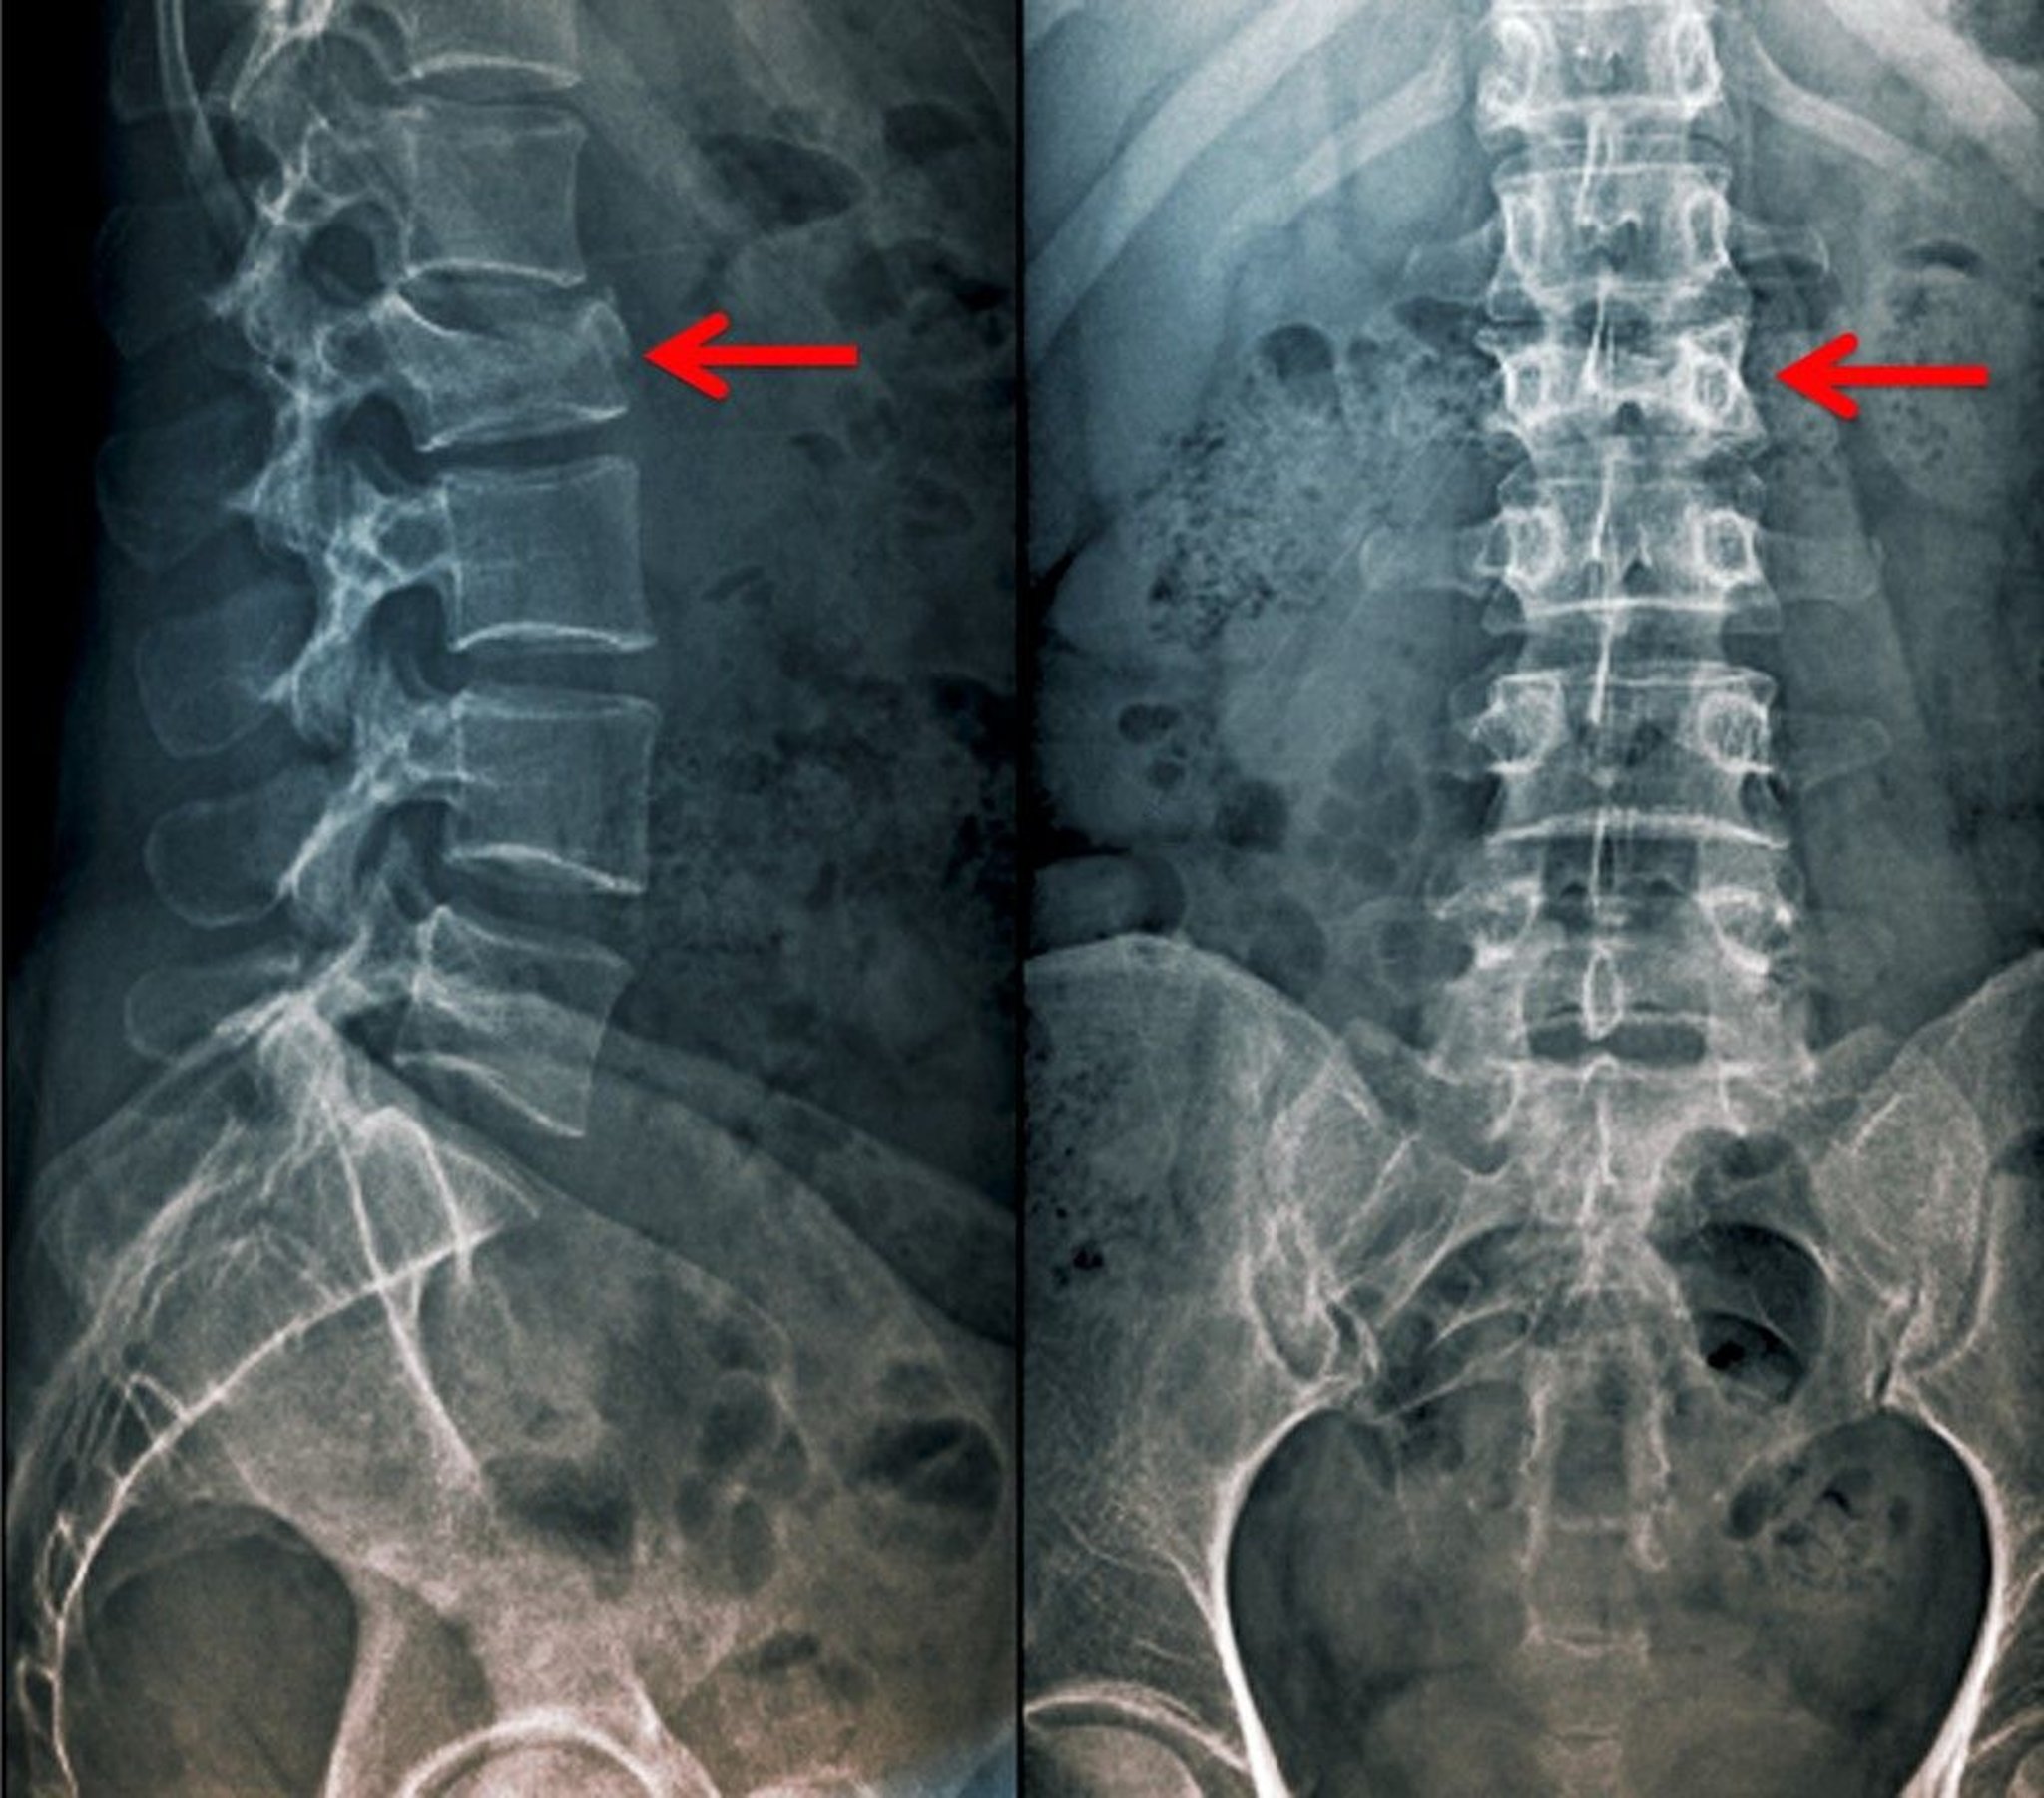

Anteroposterior and Lateral View of a Compression Fracture

This compression fracture of the 2nd lumbar vertebra is visible as a loss of vertebral body height in the anteroposterior as well as the lateral view.